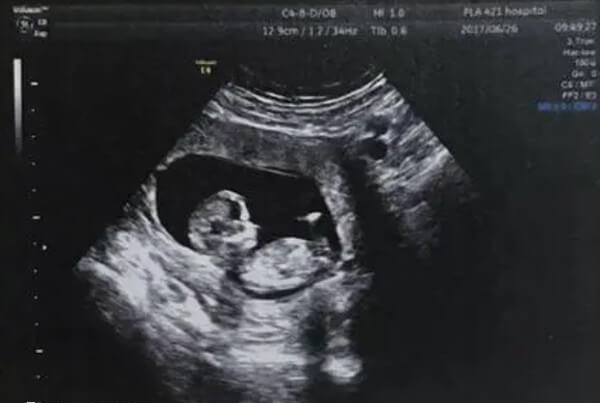

双胞胎小排畸是孕晚期的一项重要超声检查,主要用于评估胎儿在孕晚期的发育情况,排查可能存在的迟发性畸形,并为分娩提供重要参考。如果大家想要了解,双胞胎小排畸检查时间是什么时候,如下所示:

孕28-32周阶段胎儿器官发育基本完善,羊水量适中,便于观察双胎结构及排除迟发性畸形(如脑积水、肠道闭锁等)。这时进行双胞胎小排畸,可评估胎儿生长趋势、胎盘功能及羊水分布,尤其对双胎输血综合征等并发症的筛查至关重要。

重点检查脑部(如脑积水、小头畸形)、心脏、腹部脏器(如肾脏、肠道)、脊柱和四肢等,排查孕中期未发现的迟发性畸形,如部分泌尿系统畸形、肠道闭锁等。

测量胎儿双顶径、股骨长、腹围等指标,评估胎儿大小是否与孕周相符,判断是否存在生长受限或过大情况。